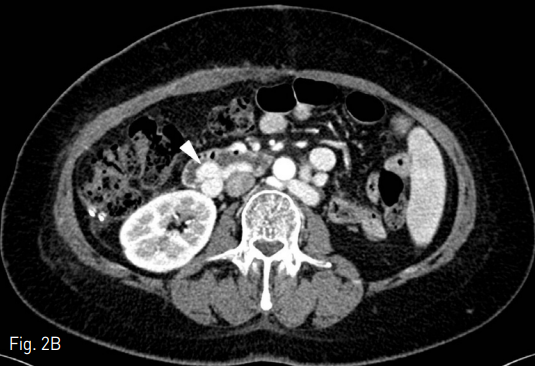

마지막 내시경적 치료 이후에 검사한 전산화 단층촬영 (CT, Computed Tomography)에서 십이지장 제3부와 제4부에 걸쳐 hemoclipping된 십이지장 정맥류가 있음 (Fig. 2A-C). 십이지장 정맥류는 상장간막정맥에서 기시하여 좌측 부신장정맥으로 연결되는 장간막신장정맥단락(mesenterorenal shunt)에 위치했음.

Fig. 2

A. Varix with hemoclipping (arrow) is seen at the 3rd/4th portion of duodenum.

B-C. Duodenal varix (arrowhead) is connected with tortuous and dilated mesenterorenal shunt (open arrow). The mesenterorenal shunt starts from superior mesenteric vein and drains to left accessory renal vein (not seen on this image).